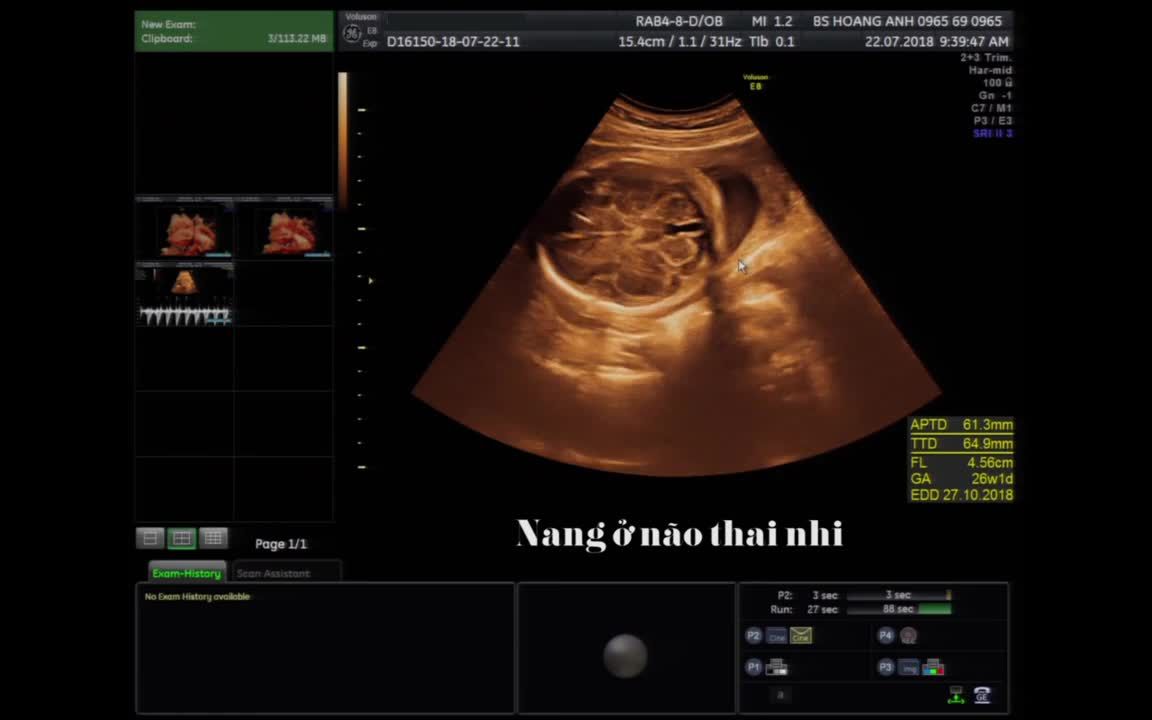

Siêu âm thai có nang não thất tuần 34, 36 và tuần 38